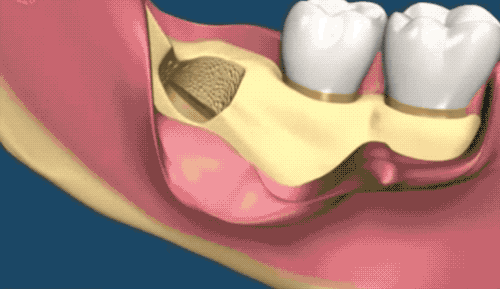

难度二

地狱模式

这种款式的横阻生智齿。一般生长情况也分两种,一种是已经出肉的,一种是还未出肉的,操作都差不多,我们就直接看下图的介绍了。

露出牙槽骨后,先削除一部分骨头,露出躺卧如睡美人的横阻生智齿…如果是已经出肉的智齿,就没这一步了。

请出那令人闻声丧胆的牙科涡轮机,先分割智齿,撬出块头过大的牙冠来…再把牙根磨切两半,依次撬出来。